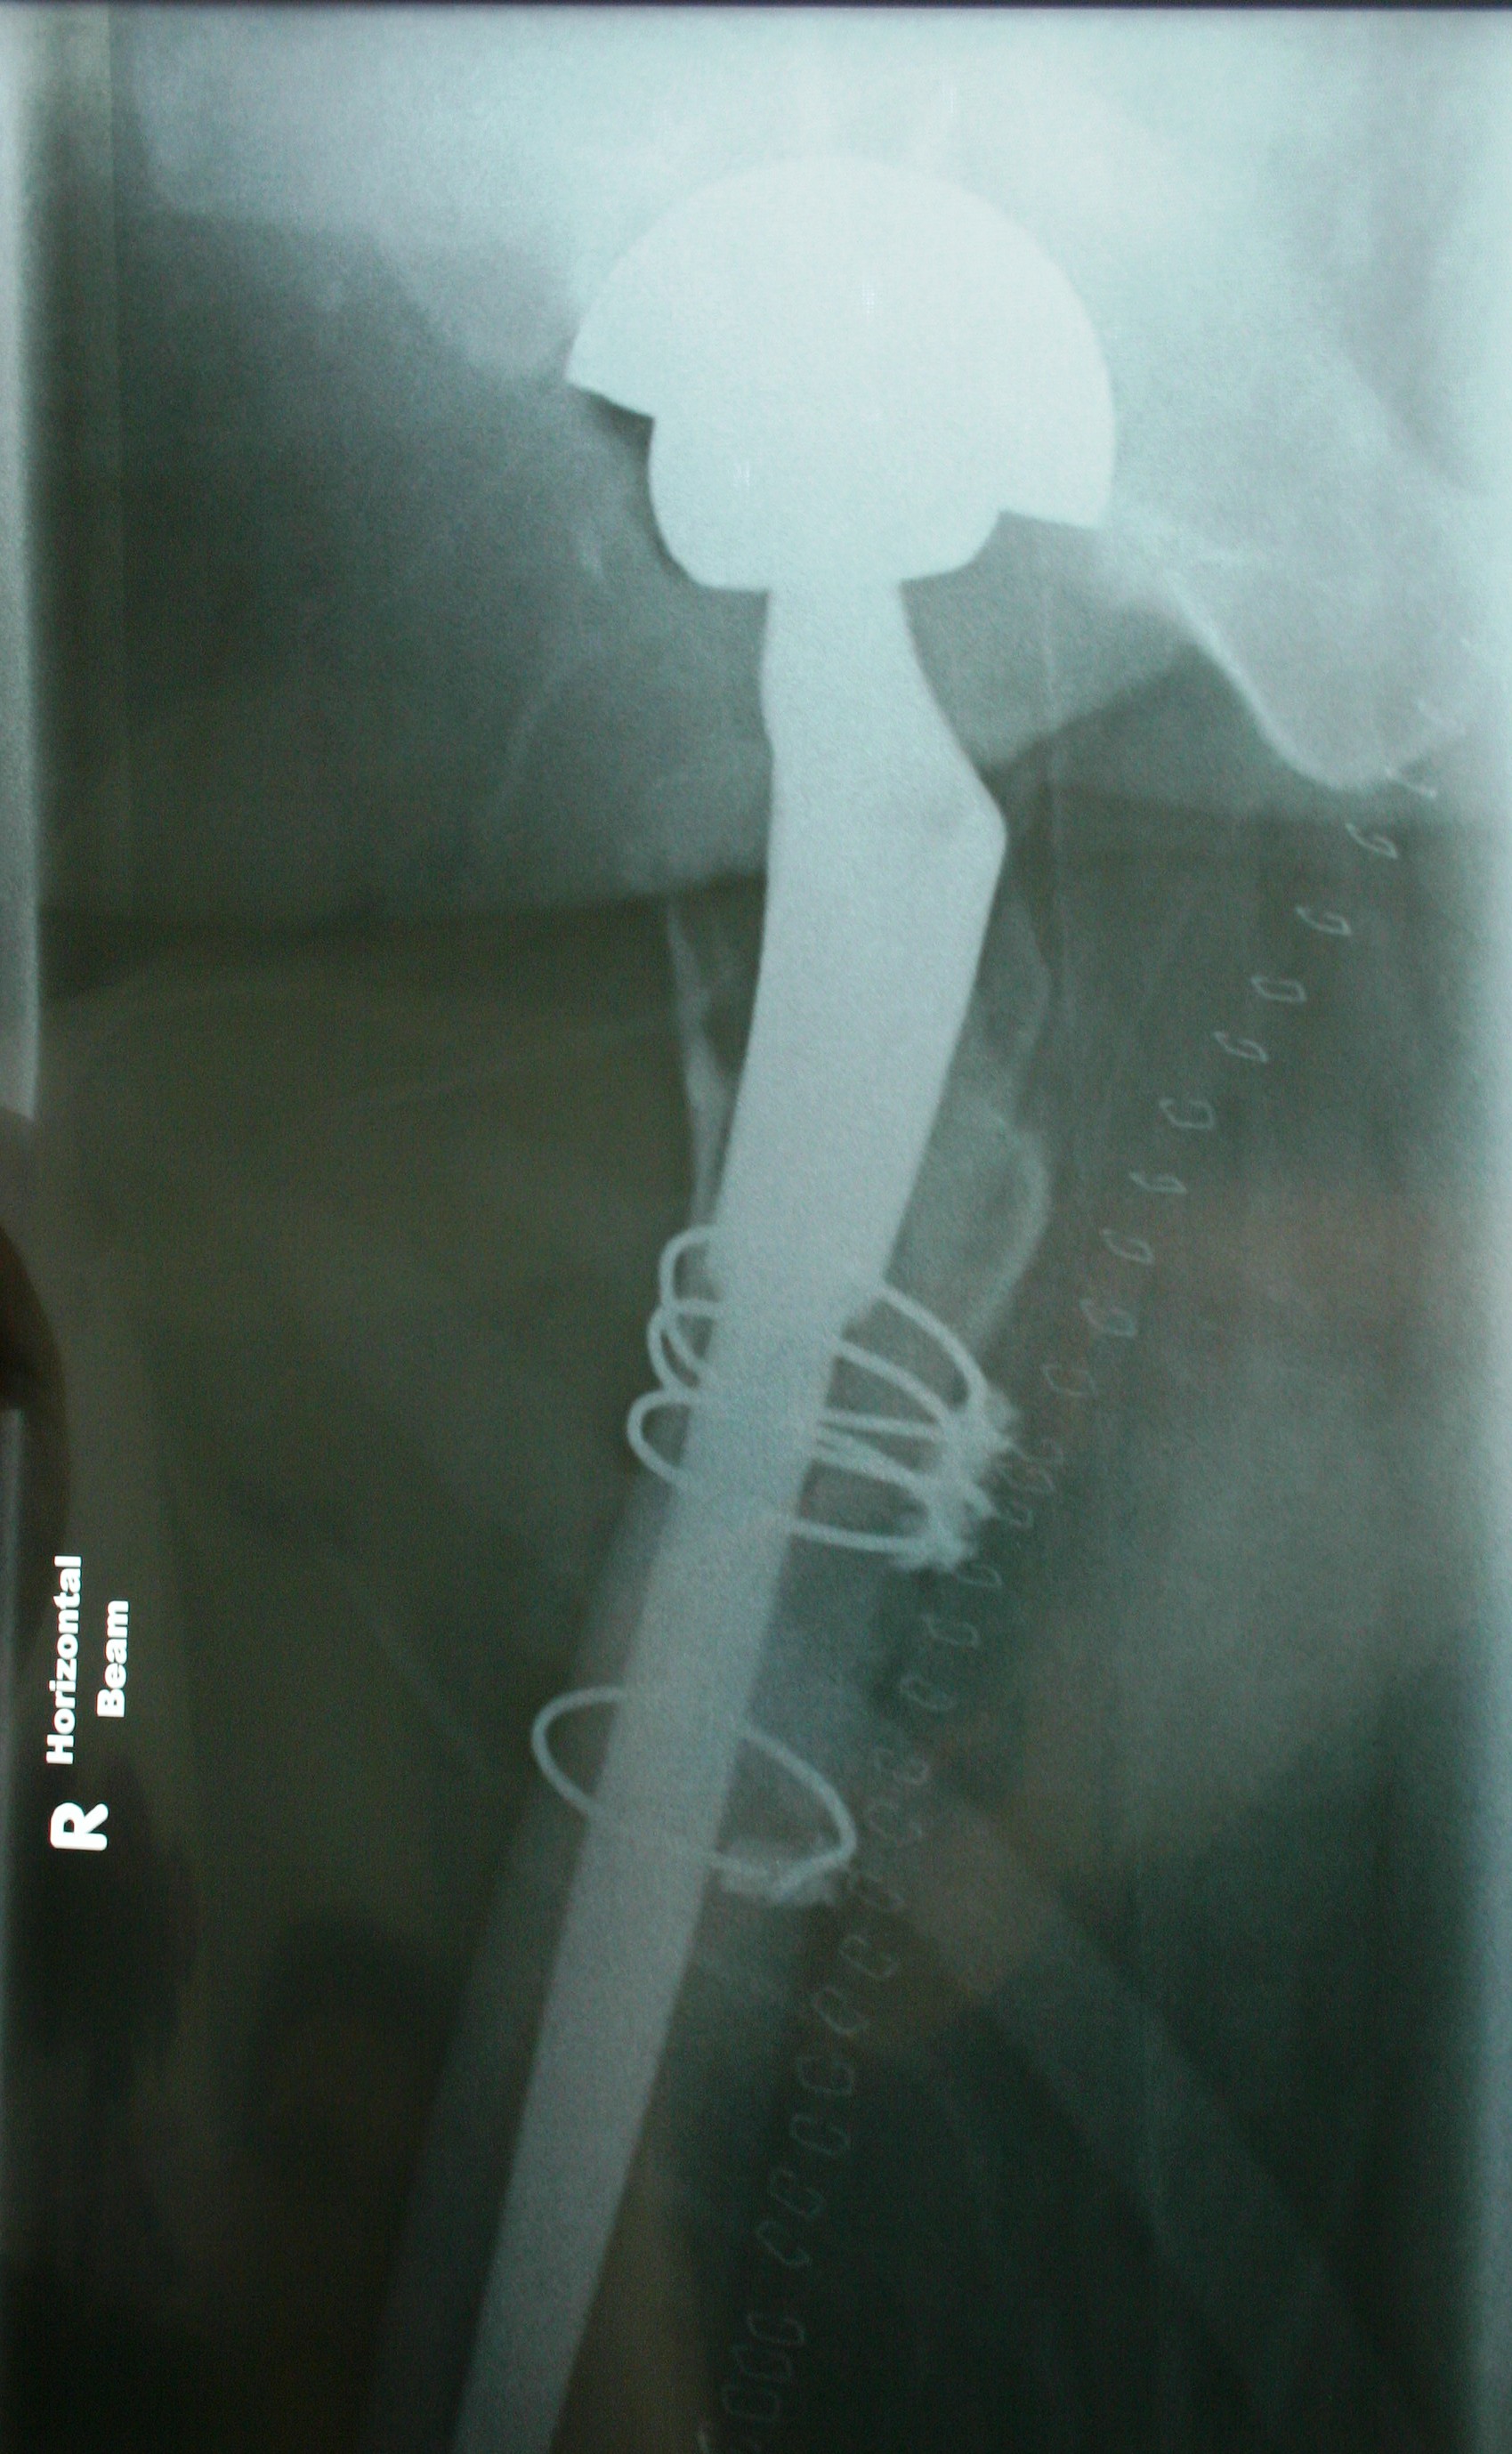

Here are the X-Rays of the revised hip – wired for everything except Digital FM, it seems!

- Split the femur to remove the previous Birmingham Spectron (S&N) femoral implant and remove excess glue and metallosis gunk.

- Bone graft to fill voids – wired femur back together to give bone strength while it heals – the fourth wire is to strengthen the mid femur because the new implant has a longer stem.

- New stem is press-fit.

- Then remove old acetabular cup – bone graft to fill out the void left – new cup put in and a couple of screws to make sure everything stays in place.

- Femoral head and cup are now inserted – ceramic on ceramic.

- The revision system is by Zimmer.

- To the right you can see the 38 or so stainless steel staples used to close the wound – removed on day 12 with only a few stings – no drama.

- The quality is not very good – taken on day one with me lying on a normal hospital bed and a very creative X-Ray team finding ways to get the required shots without moving me, the pain pump and the two drips too much – a real plumber’s muddle!

- Next week before I see the surgeon I will get a new set of X-Rays which should be a little crisper!